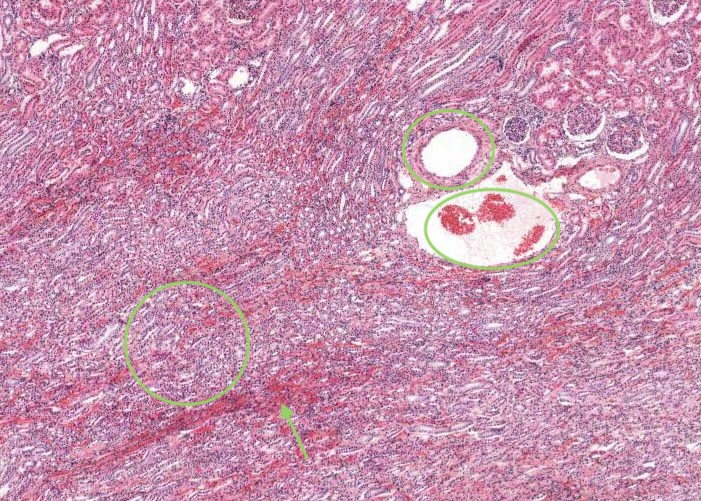

A renal pyramid is a conical structure in the medulla formed by the tubules. Humans may have 8-12 pyramids. The base of the pyramid faces the cortex and the apex (papilla) projects into the minor calyx

The renal papilla is the tip of each pyramid. The indented epithelial surface at the tip of the papilla (area cribosa) may represent the merging of collecting ducts to form a papillary duct (duct of Bellini) that empties urine into the minor calyx. The collecting ducts are wider in diameter and will exhibit epithelium with increasing numbers of columnar cells.

In most stained sections of kidney (including H&E), the medulla is the lighter stained inner region of the kidney. It contains straight tubules and collecting ducts with associated blood capillaries - the vasa recta. These tubules form conical shaped renal pyramids - their base faces the cortex and the apices open into a minor calyx through the tip of each pyramid (renal papilla). Pyramids are separated by extensions of the cortex (renal columns).